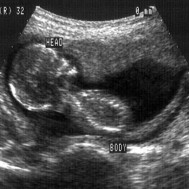

From this week onward, your size is measured from crown to heel (rather than crown to rump). You’re 26cm long and you’re putting on weight! Swallowing practice continues, and some of the liquid is moved to your bowel, where meconium accumulates.[1]

As the brain and nerve endings continue to develop, you may experiment with your sense of touch.[2] In this photo the baby is touching her ear.